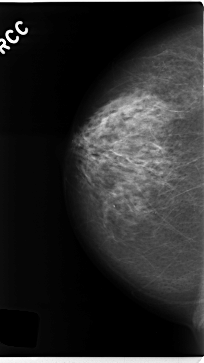

C_0228_1.RIGHT_CC

RIGHT_CC LINES 4712 PIXELS_PER_LINE 2648 BITS_PER_PIXEL 12 RESOLUTION 50 NON_OVERLAY

RIGHT_MLO LINES 4704 PIXELS_PER_LINE 2672 BITS_PER_PIXEL 12 RESOLUTION 50 NON_OVERLAY